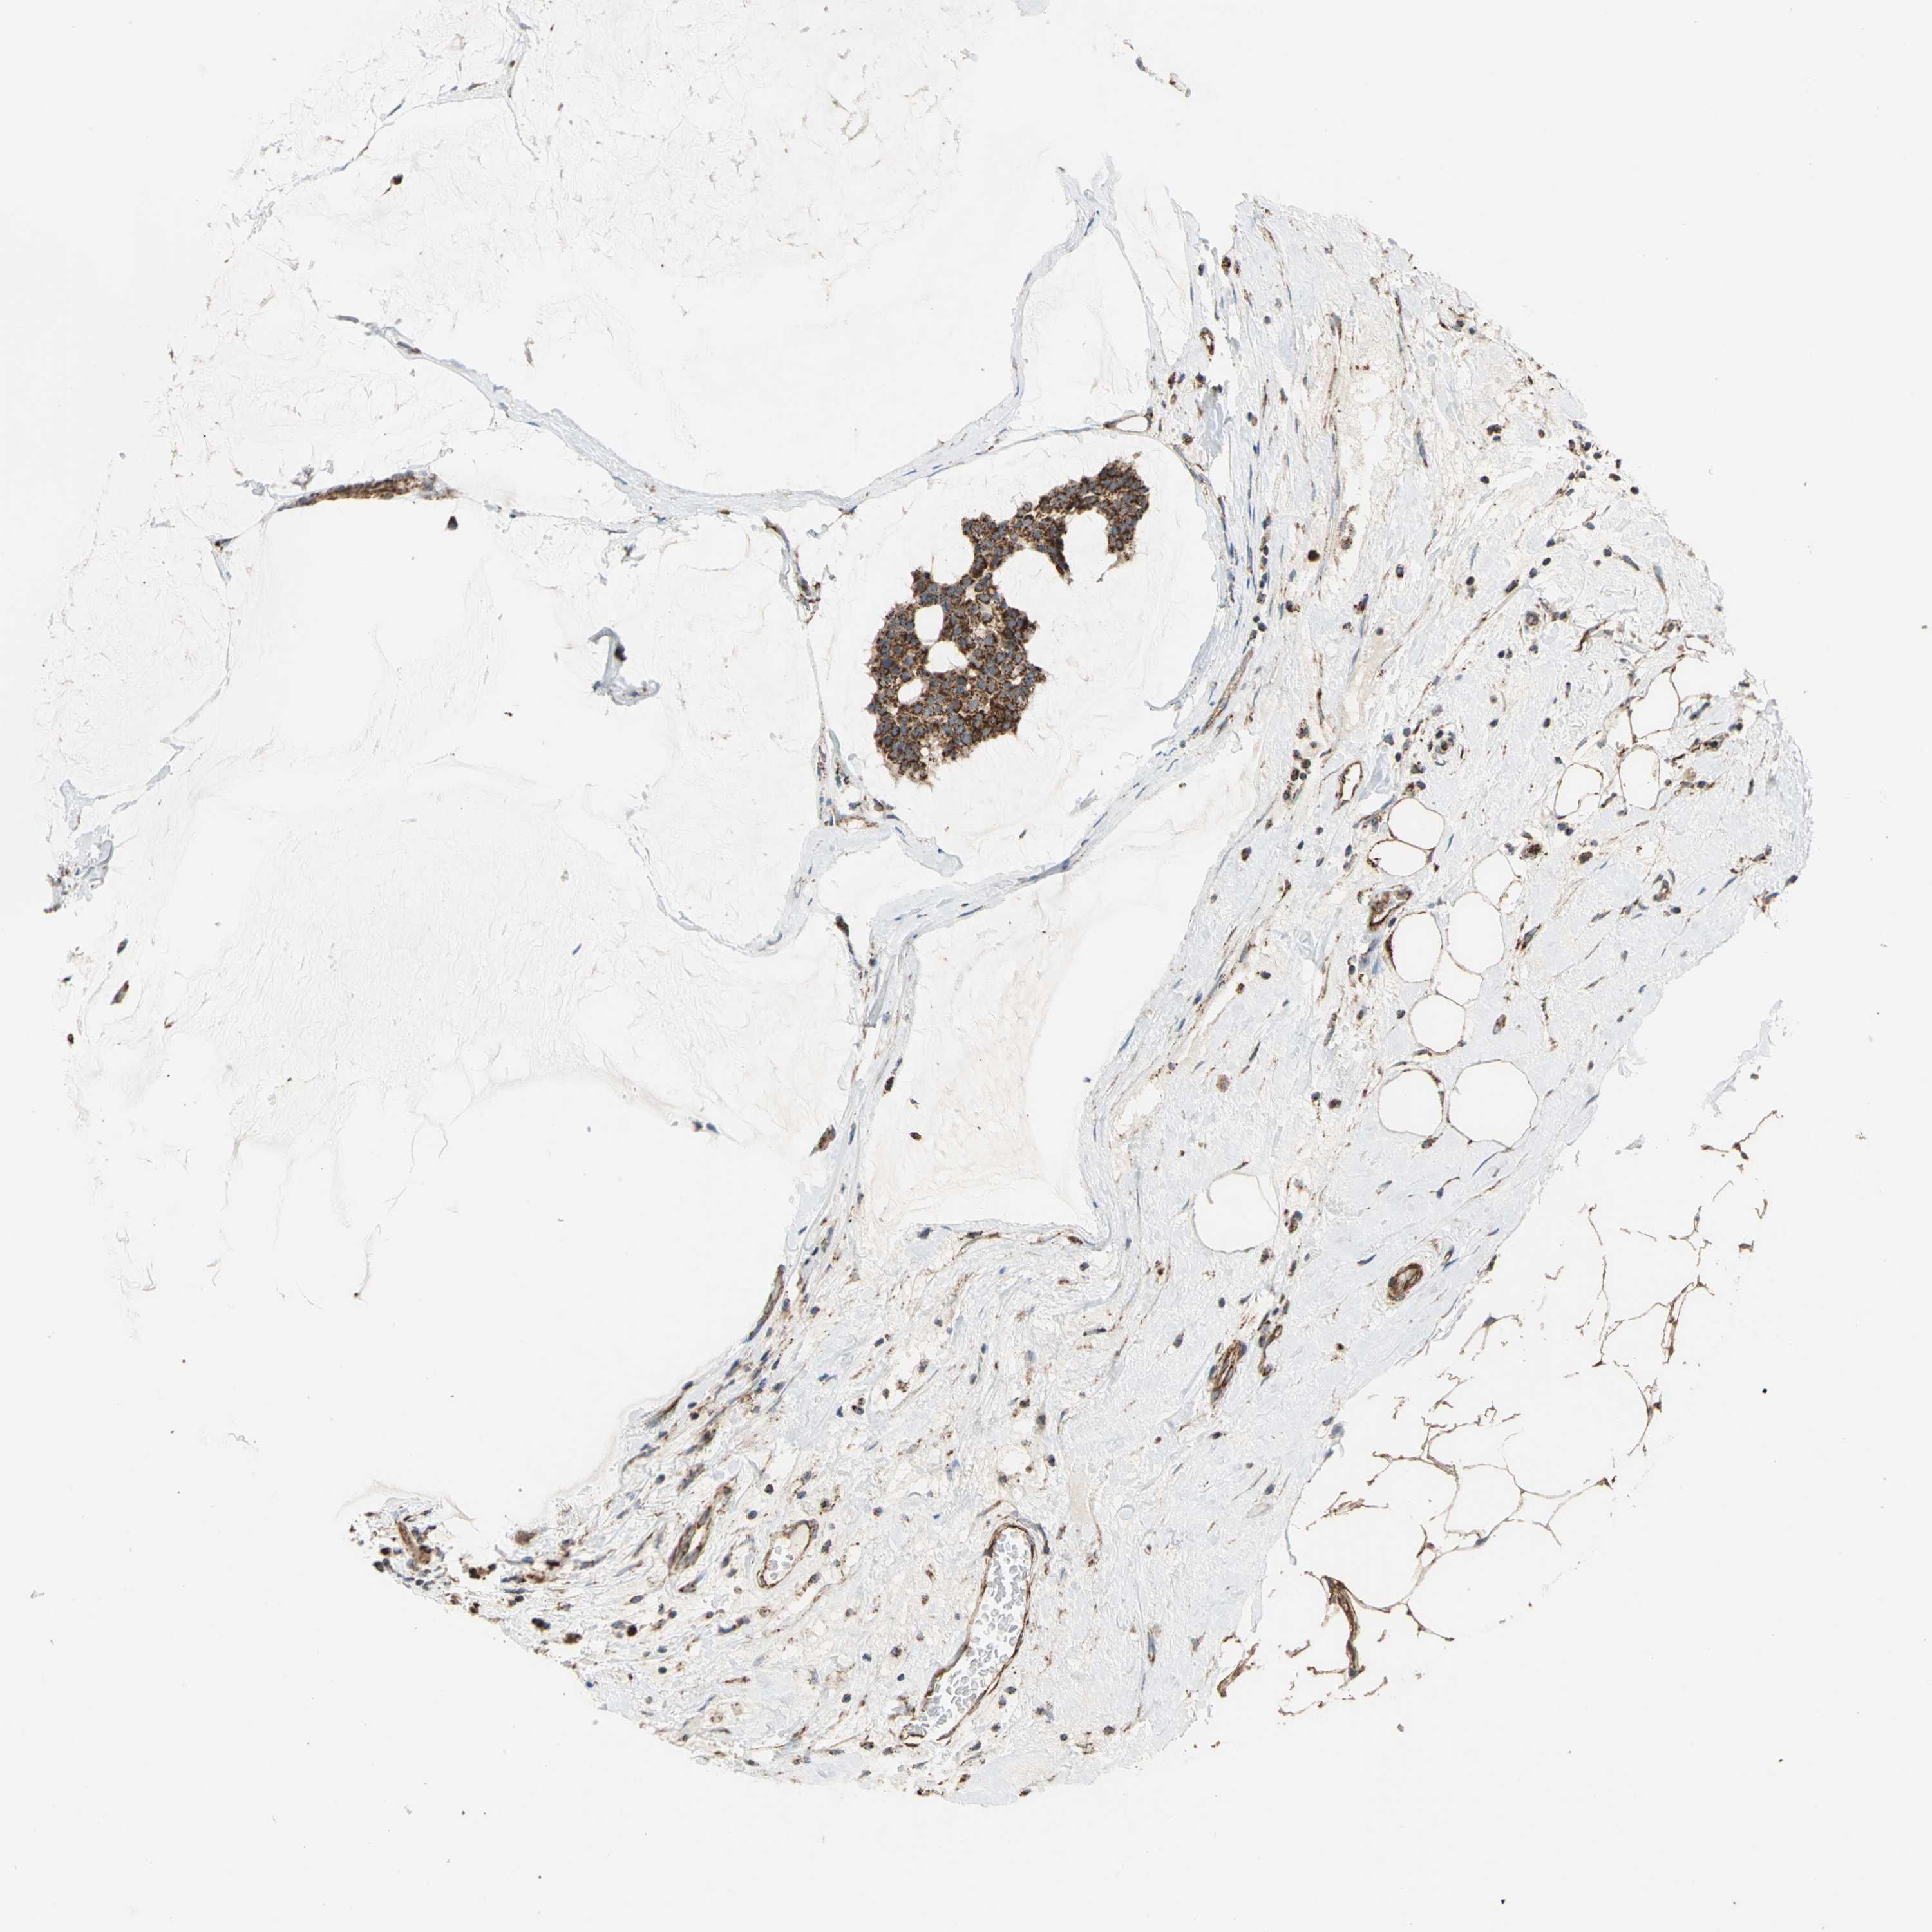

BRCA TCGA BRCA VALIDATION PROTEIN EXPRESSION